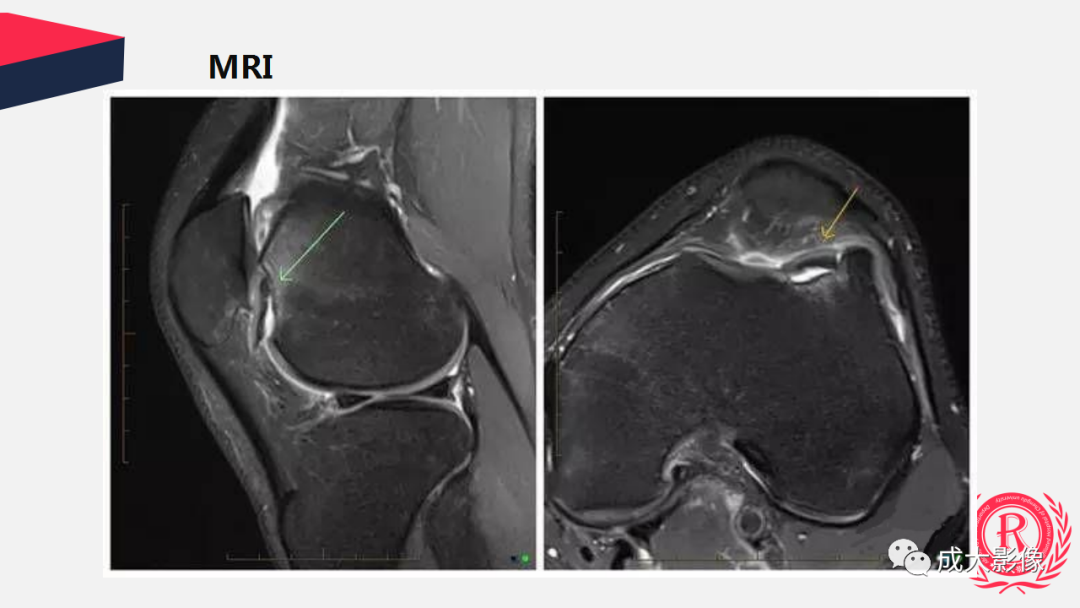

你考虑什么诊断?